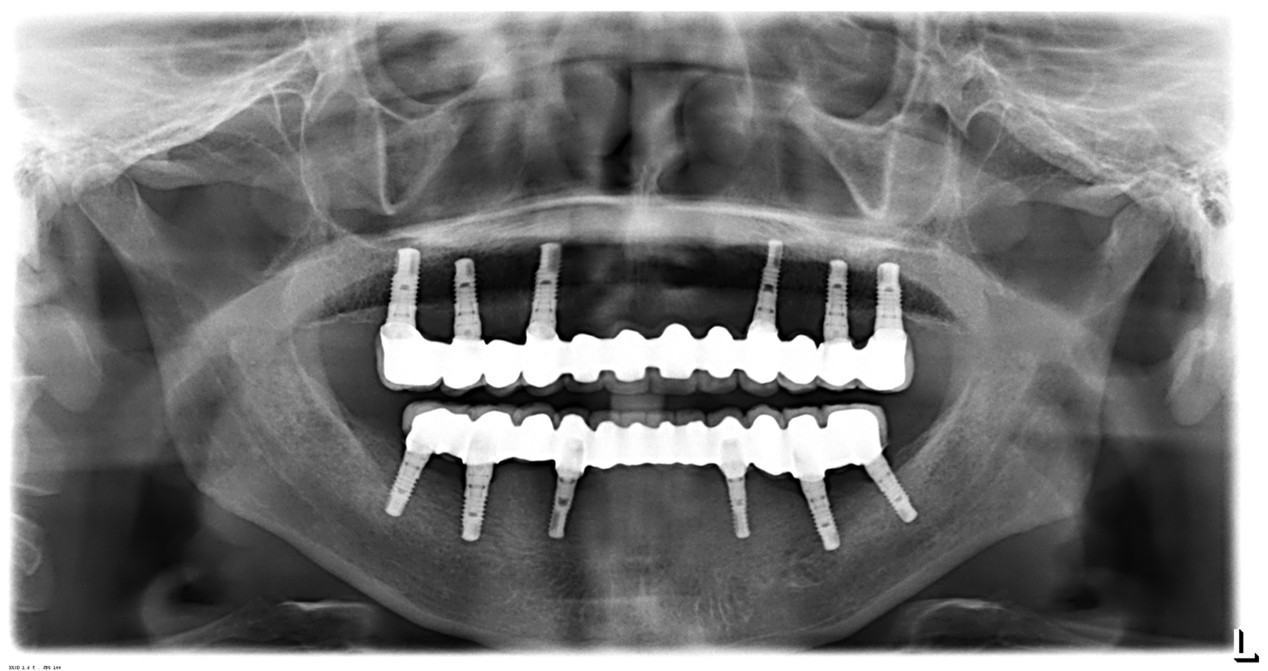

李先生長期配戴活動假牙,在日常咀嚼與使用上始終覺得不夠習慣。

初診時,李先生就很清楚地對宋醫師說:「我不追求快,只希望安全、可以用得久。」因此治療規劃並未急於進行,而是依照口腔條件、骨頭狀況與整體咬合,一步一步評估、逐步完成。

術後追蹤顯示:

- 咬合穩定

- 使用感自然

- 日常進食恢復正常

對李先生而言,這次治療不是「一次完成」,而是選擇一條能陪自己走得長遠的方式。我們始終相信,治療的價值不在速度,而在於穩定、安心,與長期的使用品質。